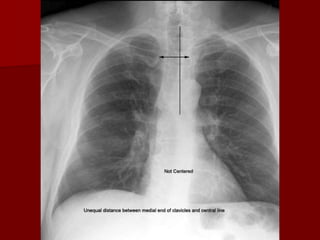

Rotation

Ideally the clavicle heads should be equidistant

from the spinous process.

Rotation of the radiograph is assessed by judging the

position of the clavicle heads and the thoracic spinous

process.

 Rotation Of patient distorts mediastinal anatomy and

makes assessment of cardiac chambers and the hilar

structures especially difficult.

Chest wall tissue also contributes to increased density

over the lower lobe fields simulating disease.